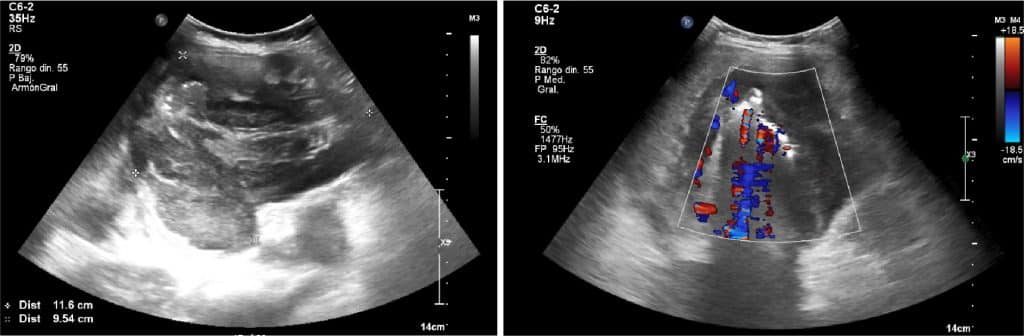

ECOGRAFÍA ABDOMINAL

En la ecografía abdominal, se observa una masa intraperitoneal de aprox. 10 cm de diámetro máximo localizado en el hemiabdomen derecho, de aspecto heterogéneo y con flujo al Doppler color.